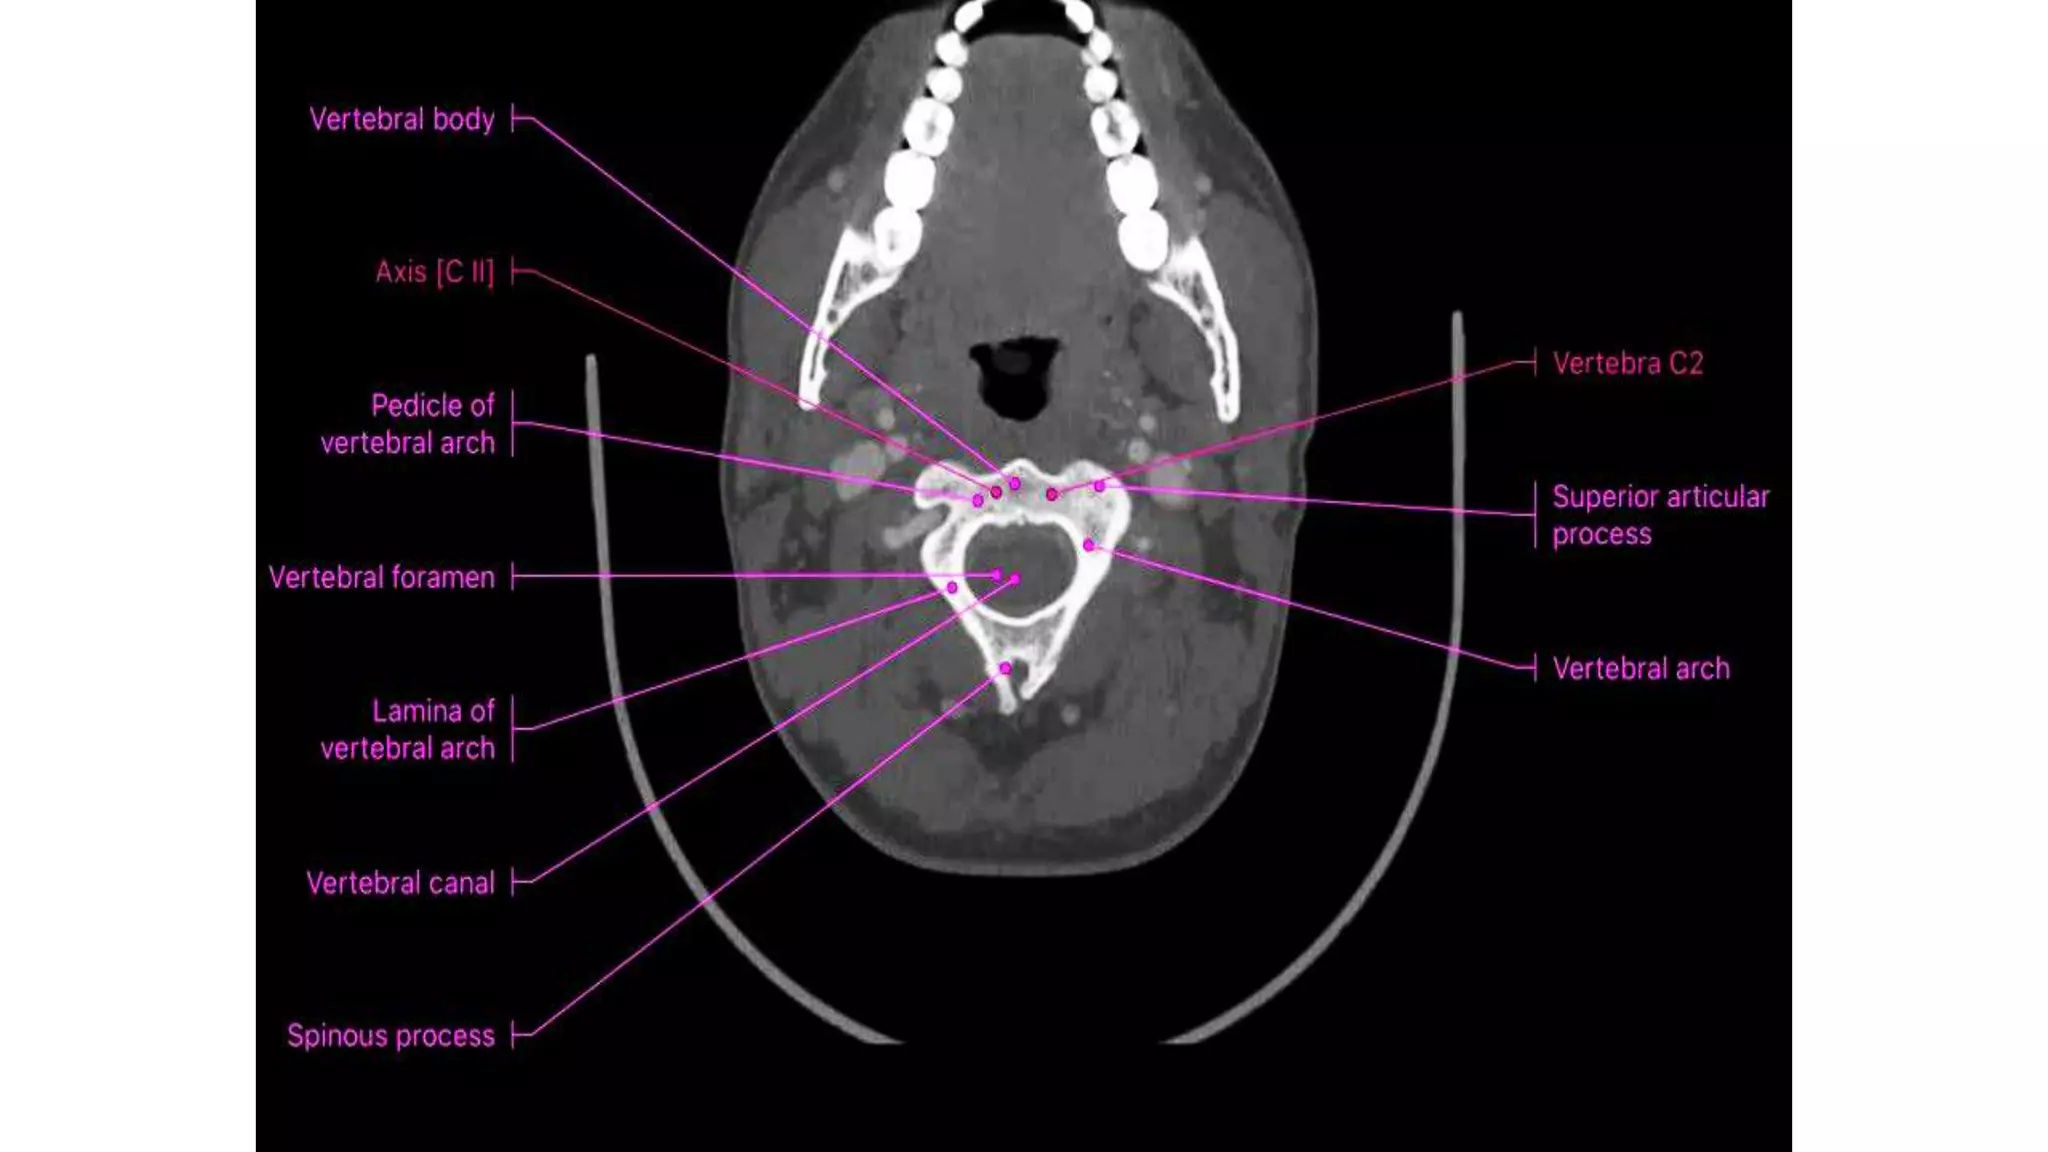

VERTEBRAL CANAL

• The spinal cord lies within a bony canal formed by adjacent vertebrae

and soft tissue elements, the vertebral canal.

• Anterior wall: the vertebral bodies of the vertebrae, intervertebral

discs, and associated ligaments,

• Lateral walls and roof: the vertebral arches and ligaments.

VERTEBRAL CANAL • Thespinal cord lies within a bony canal formed by adjacent vertebrae and soft tissue elements, the vertebral canal. • Anterior wall: the vertebral bodies of the vertebrae, intervertebral discs, and associated ligaments, • Lateral walls and roof: the vertebral arches and ligaments.